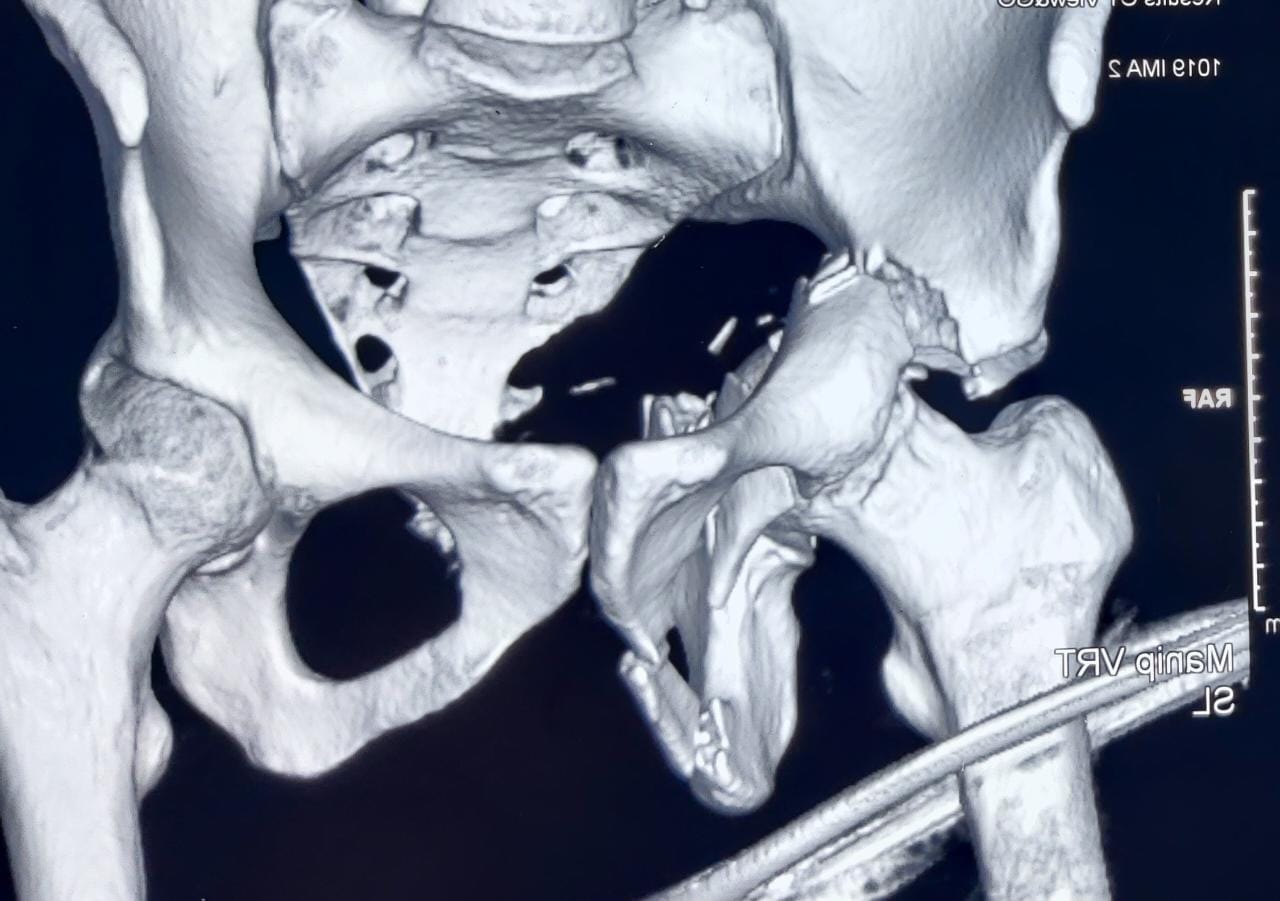

Pelvi Acetabular Trauma and Reconstruction

We as a tertiary care centre in the field of orthopaedics encounter a lot of complex trauma with extremely serious injuries around the hip

The injuries encompass hip dislocations with or without ACETABULAR fractures.

These fractures require urgent and precise surgical fixation to achieve the ultimate outcome. We at our centre routinely perform such surgeries.

Case 1